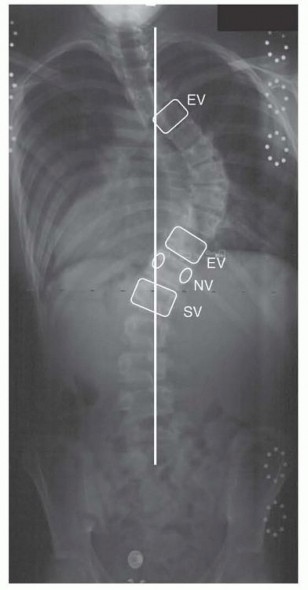

Vertebral Column Resection for Severe Rigid Spinal Deformity through an All Posterior Approach DEFINITION Pos…

Posterior Osteotomies of the Spine DEFINITION Spinal osteotomies encompass a range of techniques involving re…

Hemivertebra Excision DEFINITION A hemivertebra is a congenital anomaly of the spine that forms during the 8t…

Anterior Interbody Arthrodesis with Instrumentation for Scoliosis DEFINITION Thoracic scoliosis and thoracolu…